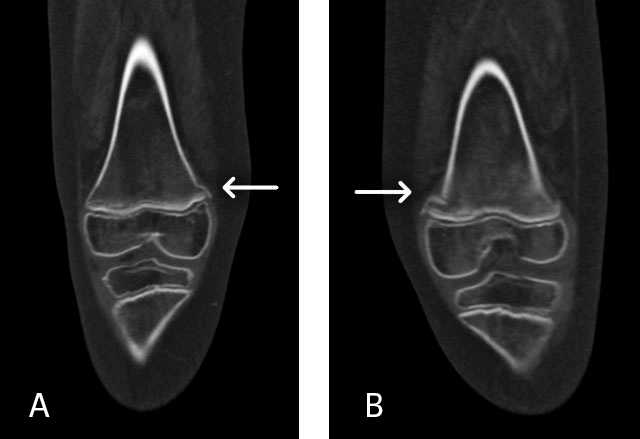

Vid ankomst till IVA var han svår att syresätta (FiO2 [inandad syrgasfraktion] på 80 procent) men cirkulatoriskt stabil. Patientens ordinarie läkare var bakjour det aktuella dygnet. Fettembolisyndrom misstänktes med tanke på den kliniska bilden. Lungröntgen tolkades initialt som påvisande aspiration. Datortomografi (DT) av lungartärer på misstanke om lungemboli (Figur 1) samt en DT av skalle på misstanke om fettemboli gjordes. Datortomografin av lungartärer bedömdes som aspirationspneumoni, och den sämre kontrastfyllnad som ses i enstaka subsegmentella artärer i både höger och vänster lunga tolkades i första hand som flödesbetingad och antibiotika sattes in. DT av knän bilateralt visade odislokerade typ 2-frakturer enligt Salter–Harris frakturklassifikation (Figur 2 A och B), som gipsbehandlades.

En uppföljande MR-undersökning av hjärnan visade multipla punktformiga förändringar med diffu­sionsinskränkning bilateralt i frontalloberna, parietalt och superiort i vänster occipitallob i vit substans, subkortikalt och kortikalt (Figur 3). Bilden bedömdes som fettembolisering. Vid eftergranskning av DT lungartär bedömdes de subsegmentella förändringarna i samtliga lunglober också som förenliga med fettembolisyndrom.

Figur 1. Datortomografi av torax med utbredda parenkymförändringar (svart pil) bilateralt som initialt tolkats som aspiration, men vid eftergranskning bedömdes som multipla fettembolier.